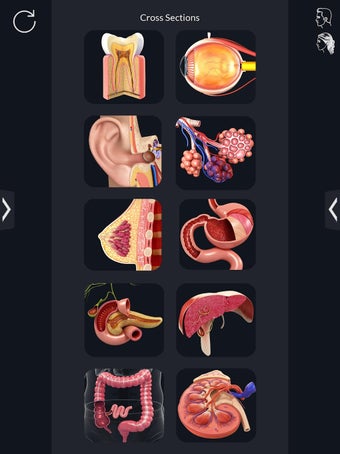

La interfaz fácil de usar de My Organs Anatomy permite una navegación sencilla, lo que facilita la selección, rayos X, ocultación y visualización de órganos individuales. La aplicación también incluye un modo de animación, opciones de búsqueda y un panel de información que proporciona información relacionada. Además, la aplicación ofrece pronunciación de audio para todos los términos anatómicos, e incluso los usuarios pueden dibujar o escribir en la pantalla y compartir capturas de pantalla.